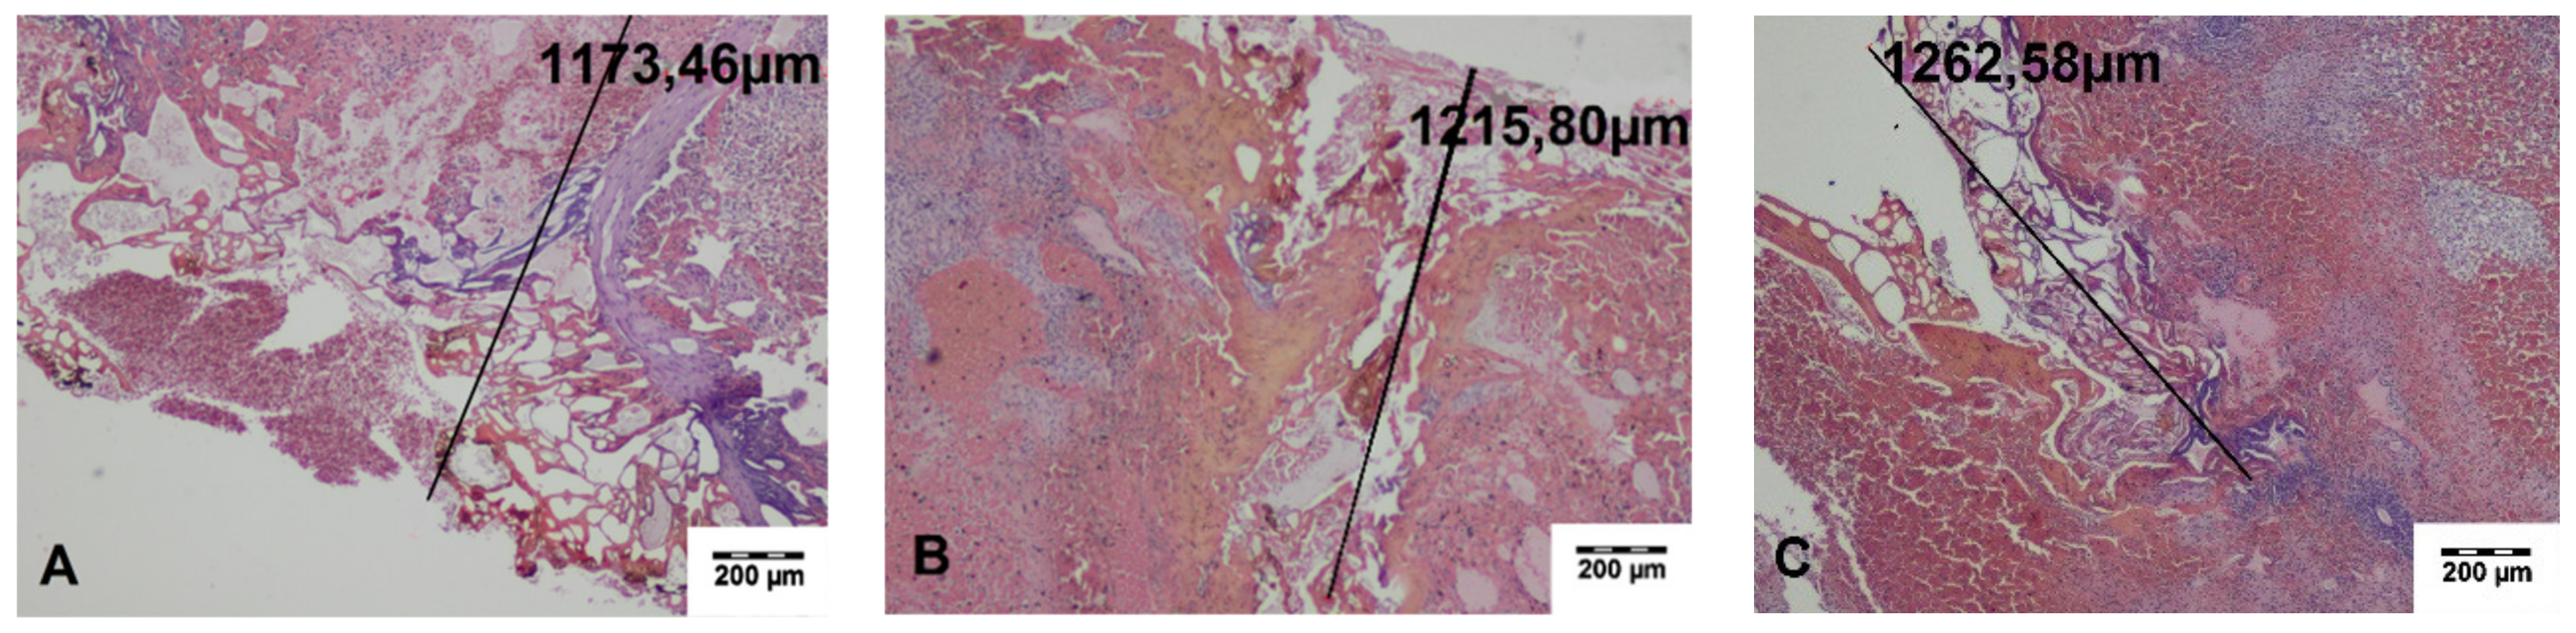

In the specimens collected during the surgery, a zone of carbonized tissue with exudation free of erythrocytes or with a small number of extravasated erythrocytes, as well as a zone of altered tissue, was visible. In the immediate vicinity of the incisions, superficial carbonized amorphous necrotic structures with an average width of 197.29 ± 35.99 μm for TDFL and 313.44 ± 20.89 μm for DL were found. The deeper zone was characterized by slightly shrunken cells with preserved cell nuclei, sharply demarcated from the surrounding normal tissue. The average width of both zones of thermal tissue damage was 655.26 ± 107.70 μm for TDFL and 1413.37 ± 111.85 μm for DL (Figure 3 and Figure 4, Table 2).

Figure 4. Histopathological sections of the spleen fragments collected intraoperatively at the site of cutting with the diode laser (DL). Black lines indicate the width of the entire zone of thermal damage (HE staining). (A–C) A quite wide superficial zone of the carbonized tissue and a deeper zone of thermal changes are visible (magnification × 40).